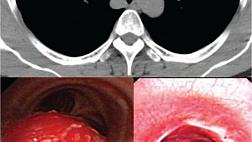

При эндоскопическом исследовании в случае бронхоэктазов в стадии ремиссии выявляется

частично диффузный бронхит I степени воспаления